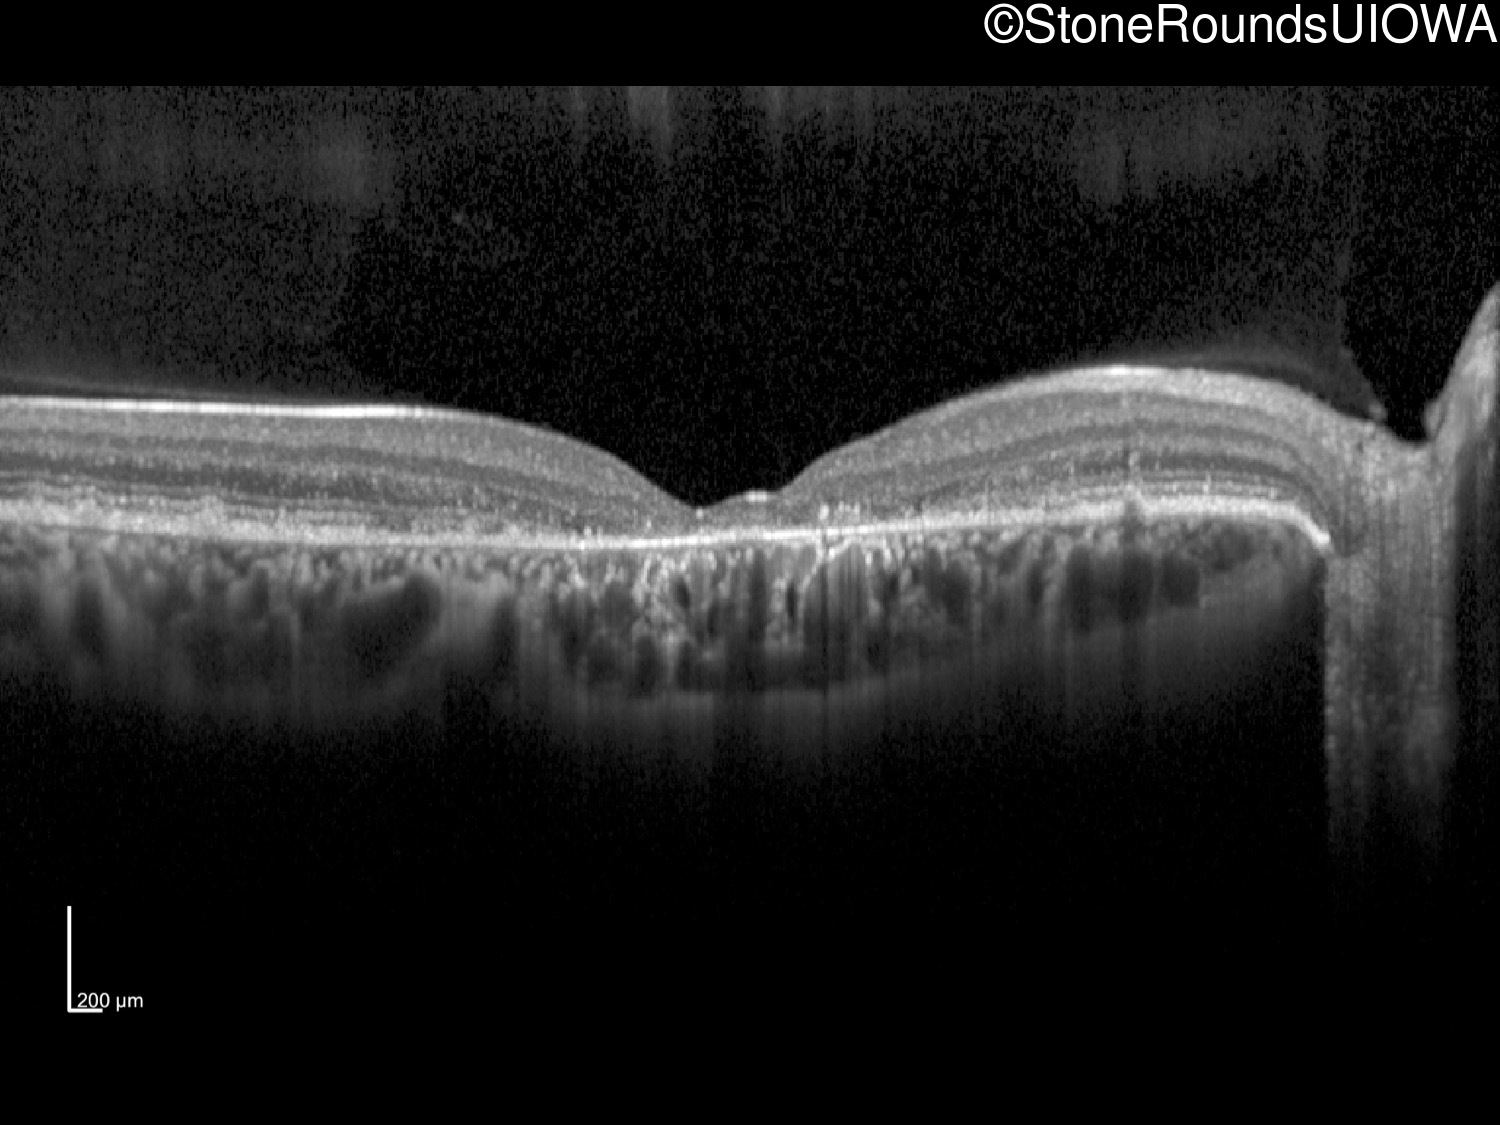

All three of the cardinal ophthalmic features of Mendelian macular dystrophies are present in this patient. The most striking features of the fundus exam are the numerous yellow flecks at the level of the RPE. Flecks are most commonly seen in AR Stargardt disease and pattern dystrophy although they may be seen in some of the rarer Mendelian maculopathies as well. The visual acuity in patients with AR Stargardt disease is often "worse than the fundus looks" while the acuity in pattern dystrophy is often quite good despite extensive flecks. The pedigree of this patient is compatible with ABCA4-associated Stargardt disease and the better than expected acuity is attributable to foveal sparing (see below). The onset of reduced acuity at age 10 is much more characteristic of ABCA4 disease than pattern dystrophy. Another feature present in this patient that is very frequently seen in Stargardt disease is peripapillary sparing. However, this sign can be seen in pattern dystrophy as well. When central atrophy is present in ABCA4-associated Stargardt disease it often somewhat shiny (which is uncommon with the geographic atrophy of pattern dystrophy or age-related macular degeneration). Some patients with ABCA4-associated Stargardt disease can have some preservation of the fovea giving a zonal "bullseye" appearance to the center of the macula. Sometimes this preservation is associated with preserved acuity as in this case. The outer nuclear layer (ONL) is much thinner than normal on OCT, indicative of photoreceptor loss. This is associated with a thinning of the ellipsoid zone which is usually many times brighter and thicker than the external limiting membrane (ELM). These two lines are essentially equal in intensity in this patient. The foveal sparing is seen on OCT only as a small bit of retinal convexity in the center of the atrophy coupled with a small bit of residual RPE flanked by bare Bruch's membrane. The presence of a robust I2e isopter on Goldmann perimetry places this patient in the least severe half of all Stargardt patients (see Schindler, et al., 2010). Most patients with ABCA4-associated disease are somewhat myopic as is this patient. Stargardt patients also tend to perform very poorly on pseudoisochromatic plates, even when their acuity is still fairly good as it is here.